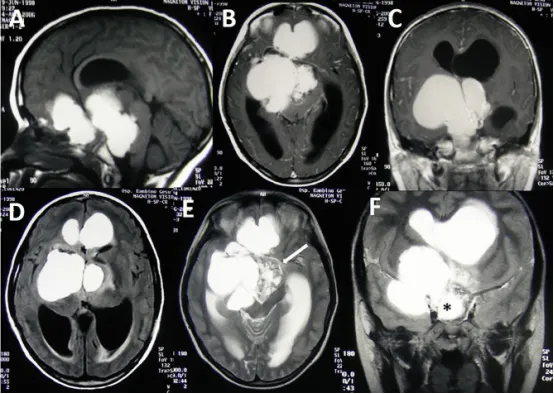

11岁男性患儿的巨大颅咽管瘤MRI表现:钆增强T1序列显示大型强化囊性成分(图A、B、C),病变范围延伸至前、中、后颅窝。同时存在明显的双侧脑室积水(图A-E)。FLAIR序列显示囊液信号高于脑脊液(图D)。值得注意的是,肿瘤实质成分占比很小(图E,箭头指示),但累及Willis环区域(图F,星号指示)。